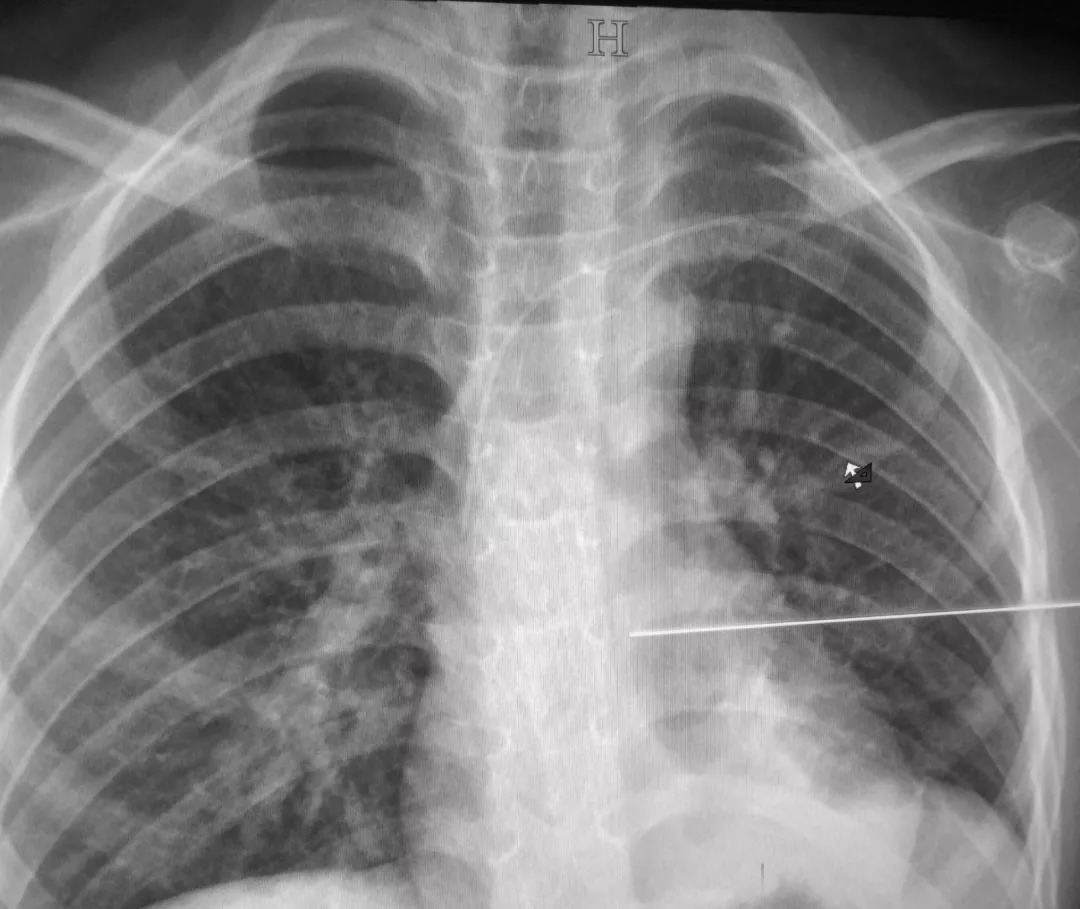

(PICC置管)

置管选取左上肢静脉穿刺,沿静脉走行达上腔静脉,并通过拍片确定导管尖端位于心脏上方的上腔静脉,手术过程顺利。